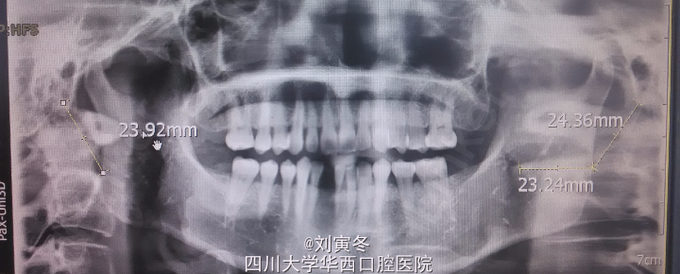

检查: 未扪及双侧颈部淋巴结肿大,双侧关节检查无明显阳性体征 口内未见明显包块病变,咬合关系良好 咽侧壁触诊可引出不适 全景片: 右侧茎突长度约3cm,左侧茎突形态异常,长度约4cm

茎突综合征又称为Eagle综合征,常见于成年人,单侧患病多见。临床表现多种多样无特异性,诊断有一定的困难。 茎突由第二鳃弓发育而来,附着有茎突舌骨韧带,茎突舌肌,咽上缩肌等口咽部肌肉。如出现茎突长度过长,方向和形态改变,均可引起咽部的疼痛不适,异物感,阻塞感等异常感觉。由于吞咽或运动时异位的茎突会刺激周围组织,导致症状加重。疼痛可放散至耳部或头部 目前,茎突长度大于3cm可认为其长度过长,冠状位上茎突与中线的角度大于40度或小于20度均可认为茎突方向异常。主要采用X线和CT检查 该病的治疗主要是保守与手术治疗。手术治疗适用于自觉症状重者,可经口咽或颈外入路切短茎突。